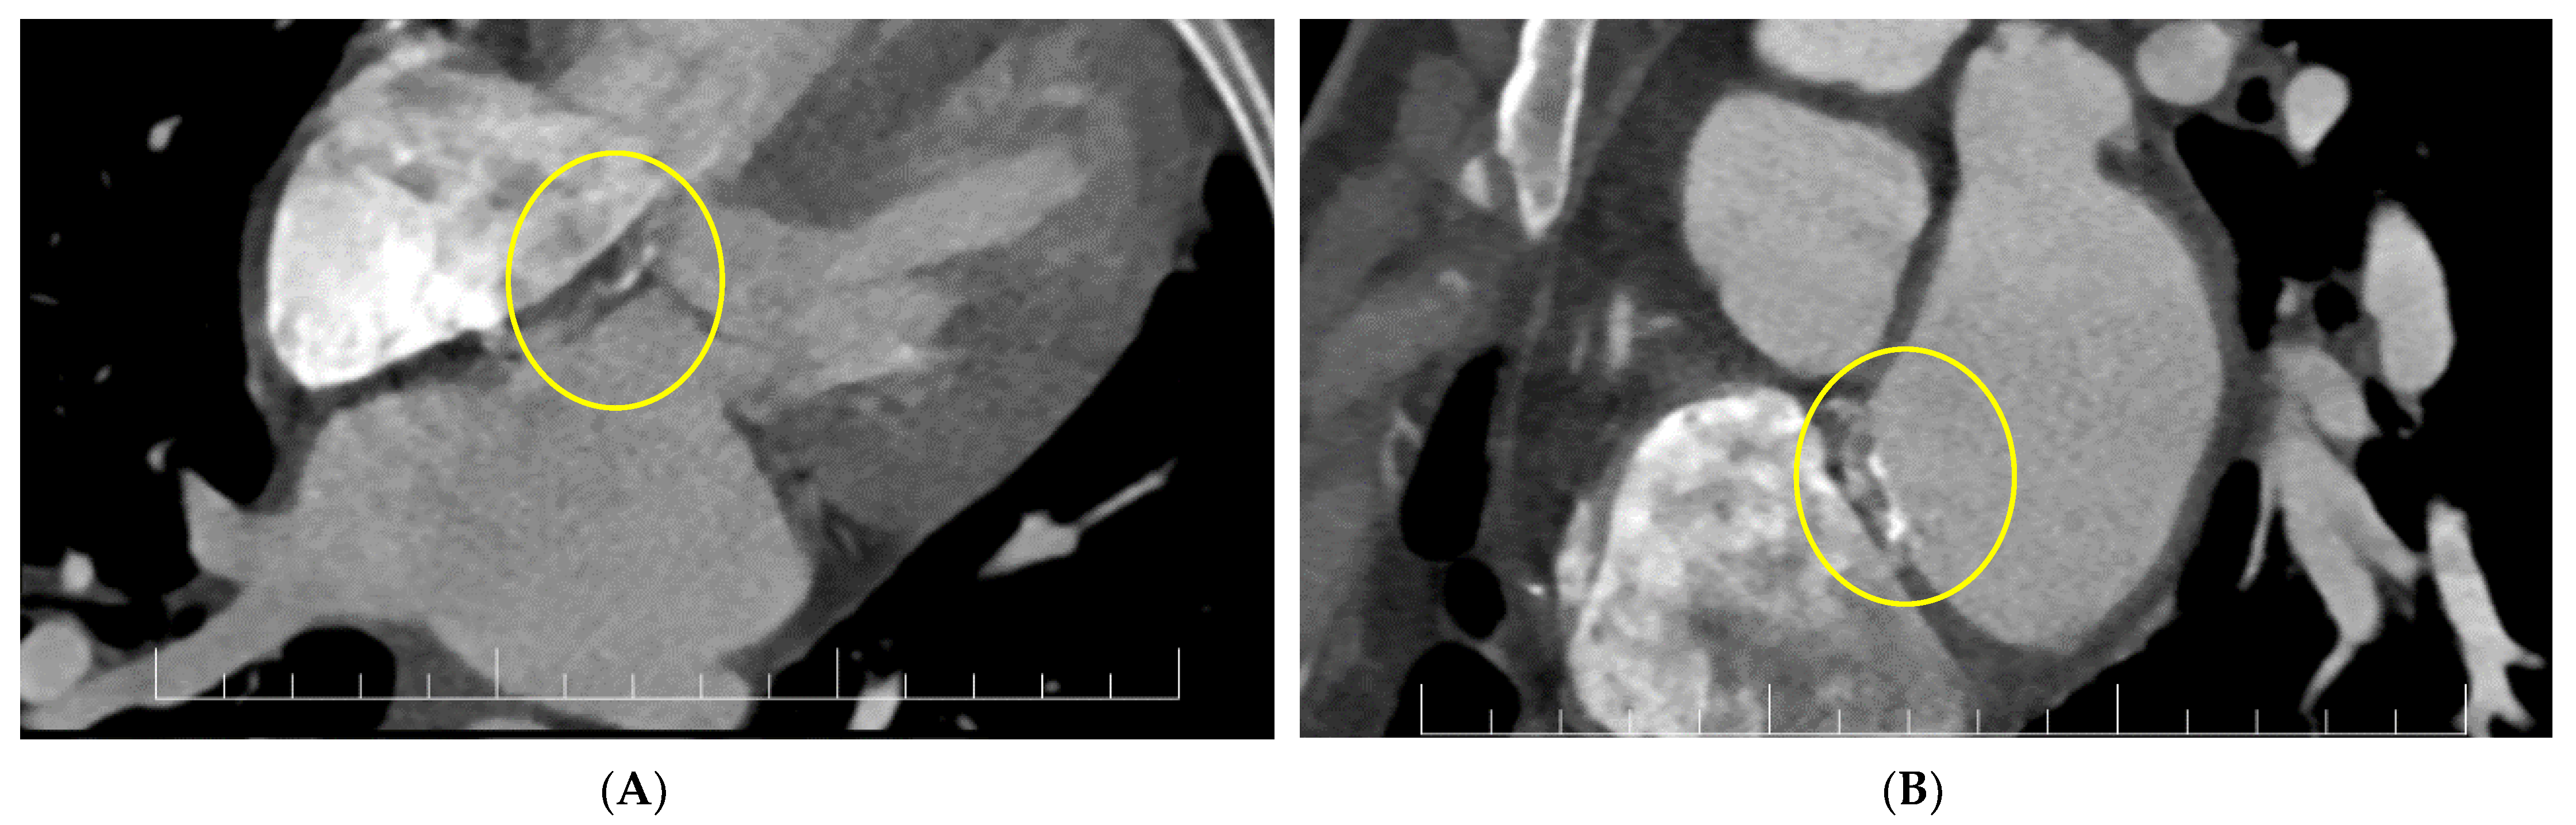

2. Case Report